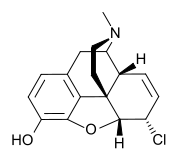

Morphides

- α-Chlorocodide (= chlorocodide)

- β-Chlorocodide

- α-Chloromorphide (= chloromorphide)

- Bromocodide

- Bromomorphide

- Chlorodihydrocodide

- Chloromorphide

- Codide

Structures

| Morphides | ||||

|---|---|---|---|---|

α-chlorocodide α-chlorocodide |

β-chlorocodide β-chlorocodide |

Bromomorphide Bromomorphide | ||

Chlorodihydrocodide. Chlorodihydrocodide. |

Chloromorphide Chloromorphide |

Codide Codide | ||